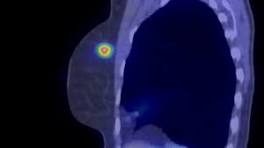

New Imaging Technique Reveals Breast Cancer in Less Than 10 Minutes "Despite the positive aspects of breast cancer screenings, i.e., reduction in the risk of death from breast cancer … there are important harms and one of ...